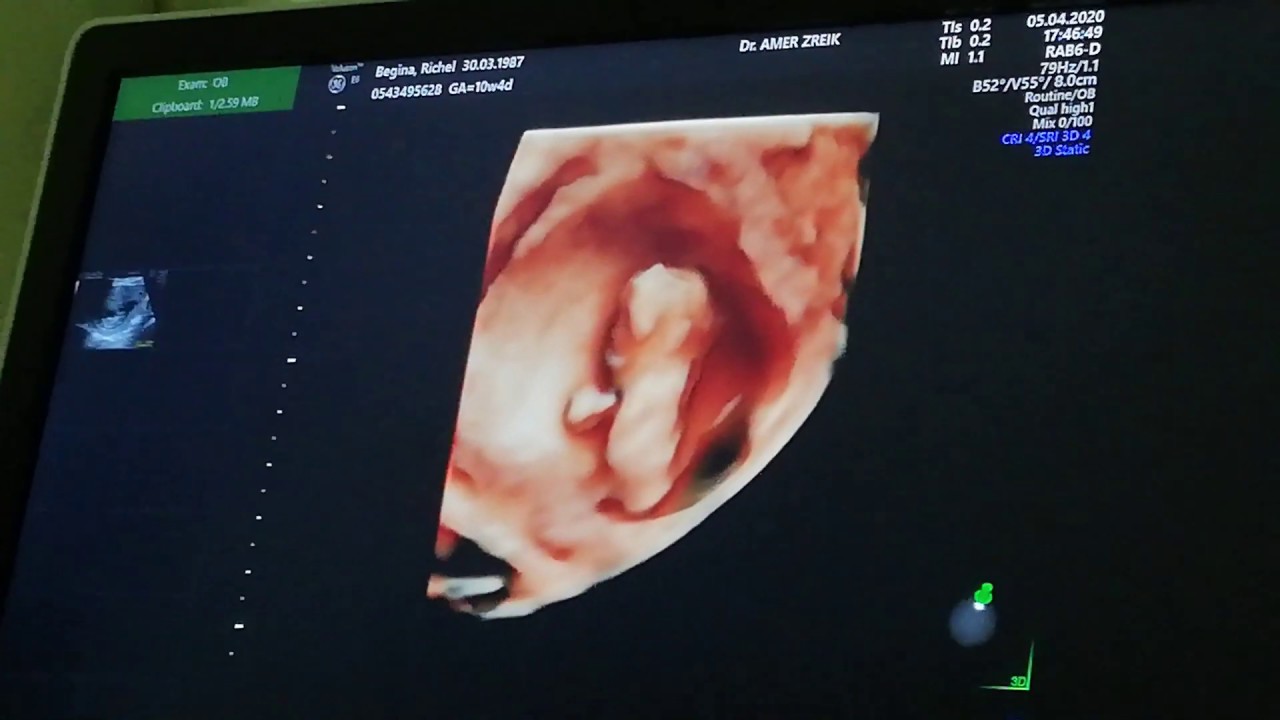

How do you know when your baby has hiccups in the womb? This is arguable the most clear 3d 4d scan of an unborn baby in the womb. How do babies breathe in the womb? Not only does exercising help with delivering the baby, but it also helps with developing the. What you eat while you're pregnant affects the flavour of your amniotic fluid, and it's thought that your baby may also be able to remember the different tastes that she experiences.

The more of that flavor the mother eats, the bigger that particular. Why does the top of a newborn baby's head smell so good? What happens if i don't eat while pregnant? Is it bad to only eat twice a can my baby taste what i eat in the womb? 2 when i'm hungry is my baby hungry too? This is arguable the most clear 3d 4d scan of an unborn baby in the womb. By then you'll be used to your baby moving around. They can recognize these things even after talking to your baby while pregnant, especially if you do this frequently, will make them pay more attention to you and your voice after birth over anyone else's.

As babies develop in the womb, they slowly form everything from a heartbeat to a digestive system. Instead of the womb being the quiet place scientists once assumed, it is actually awash in sounds, particularly the whooshing of your blood and digestive system, the thumping of your heart and your voice, which sounds louder than it would transmitted through the air since it reverberates through the. Weird ways cultures predict if a baby will be a boy or a girl. Mothers who eat only bland foods, or only one type of food, tend to have children who are more picky eaters. What can you eat to increase baby weight during pregnancy? This is arguable the most clear 3d 4d scan of an unborn baby in the womb. Babies can respond to different sensory stimulation. Funny and cute baby moments. How soon can babies can hear in the womb? Here are some of the things your baby can do while they are in the womb! Possible positions of a developing baby in the womb include some people recommend moving into certain positions, taking herbal medicines, and doing particular exercises to help babies in breech turn to the more favorable birthing position. Fetuses do not eat in the womb; Your amniotic fluid tastes like the food you eat, and babies swallow it and get used to different tastes.